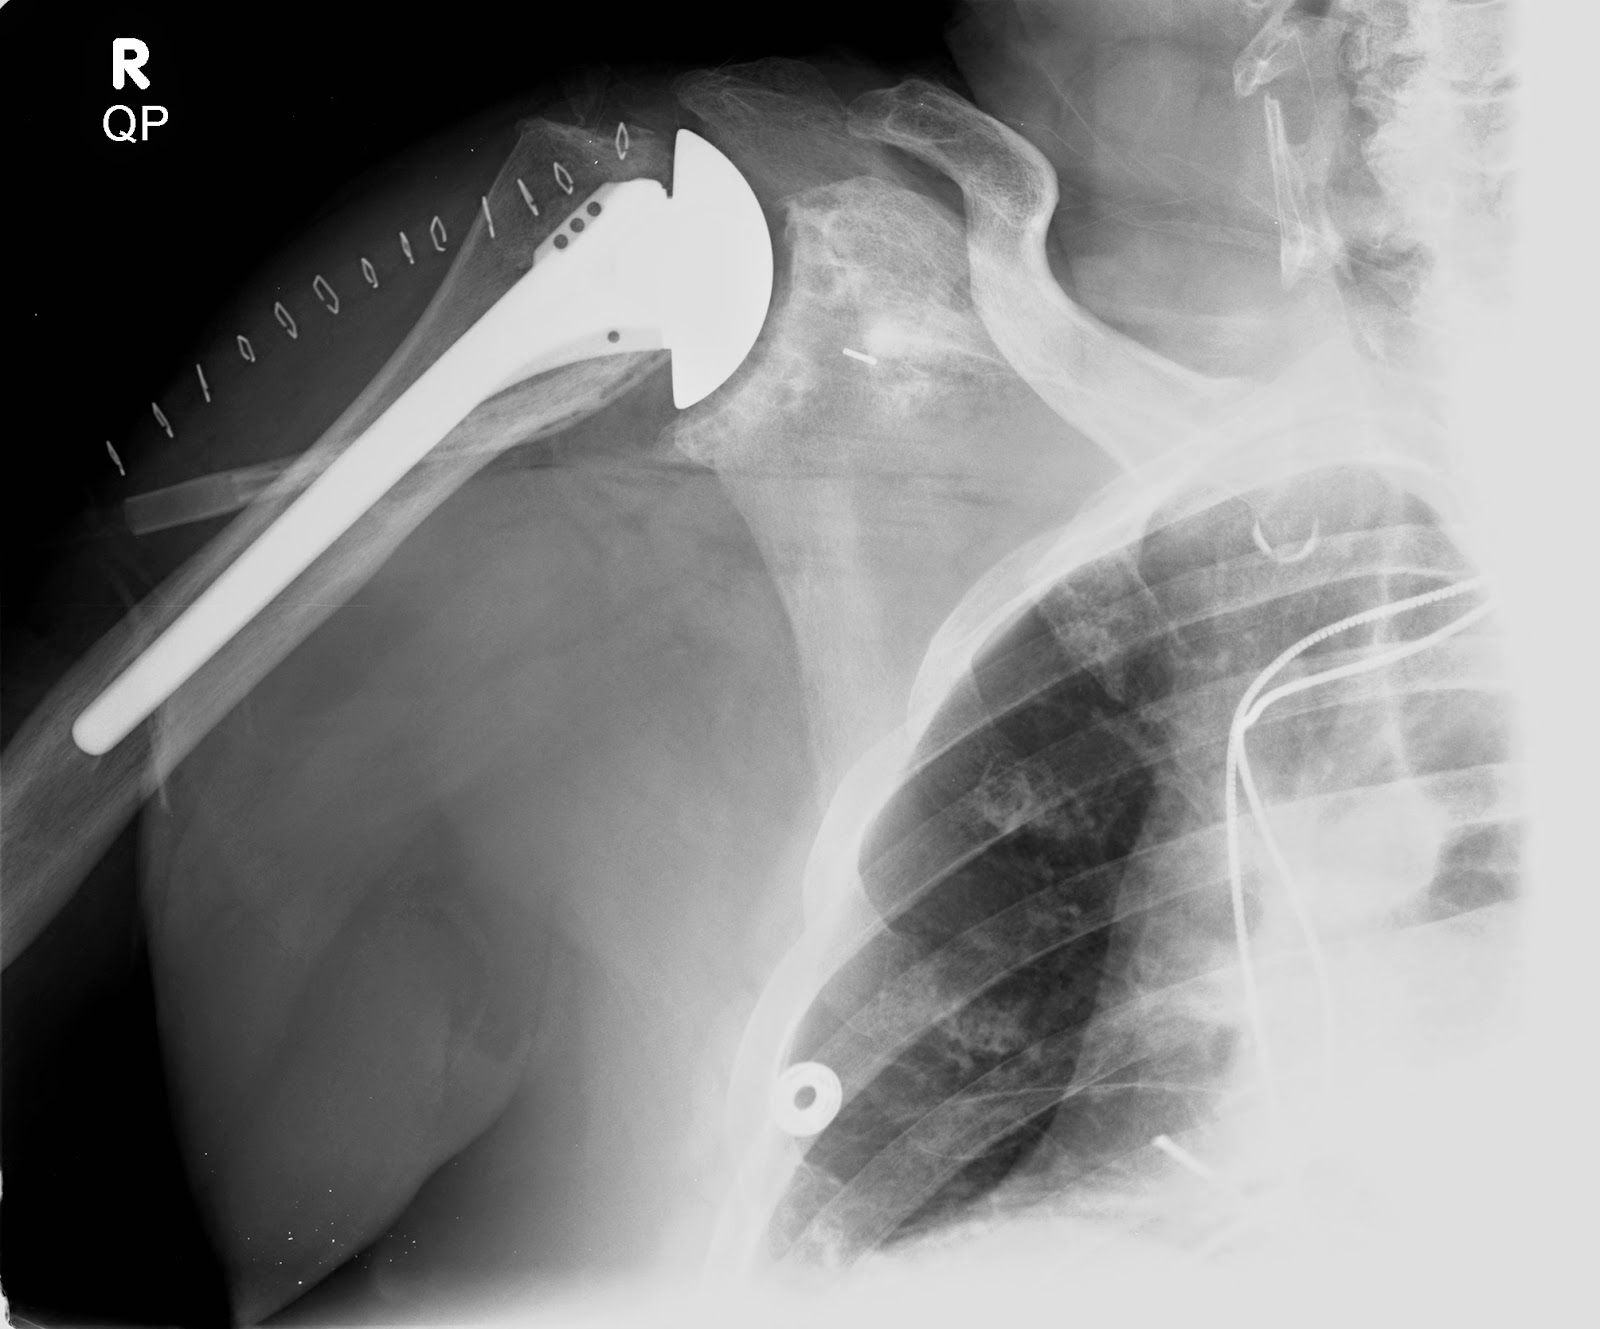

Shoulder and Elbow Surgery The radiographic analysis of a total Grashey Shoulder X Ray Positioning Standard radiography series for shoulder. The shoulder series is fundamentally composed of two orthogonal views of the glenohumeral joint including the entire. Normal ap oblique internal rotation view (grashey view). It is also known as a true ap view since the view is ap to the scapular instead of ap to. Provides better detail of cortical and trabecular bone structures. Grashey Shoulder X Ray Positioning.